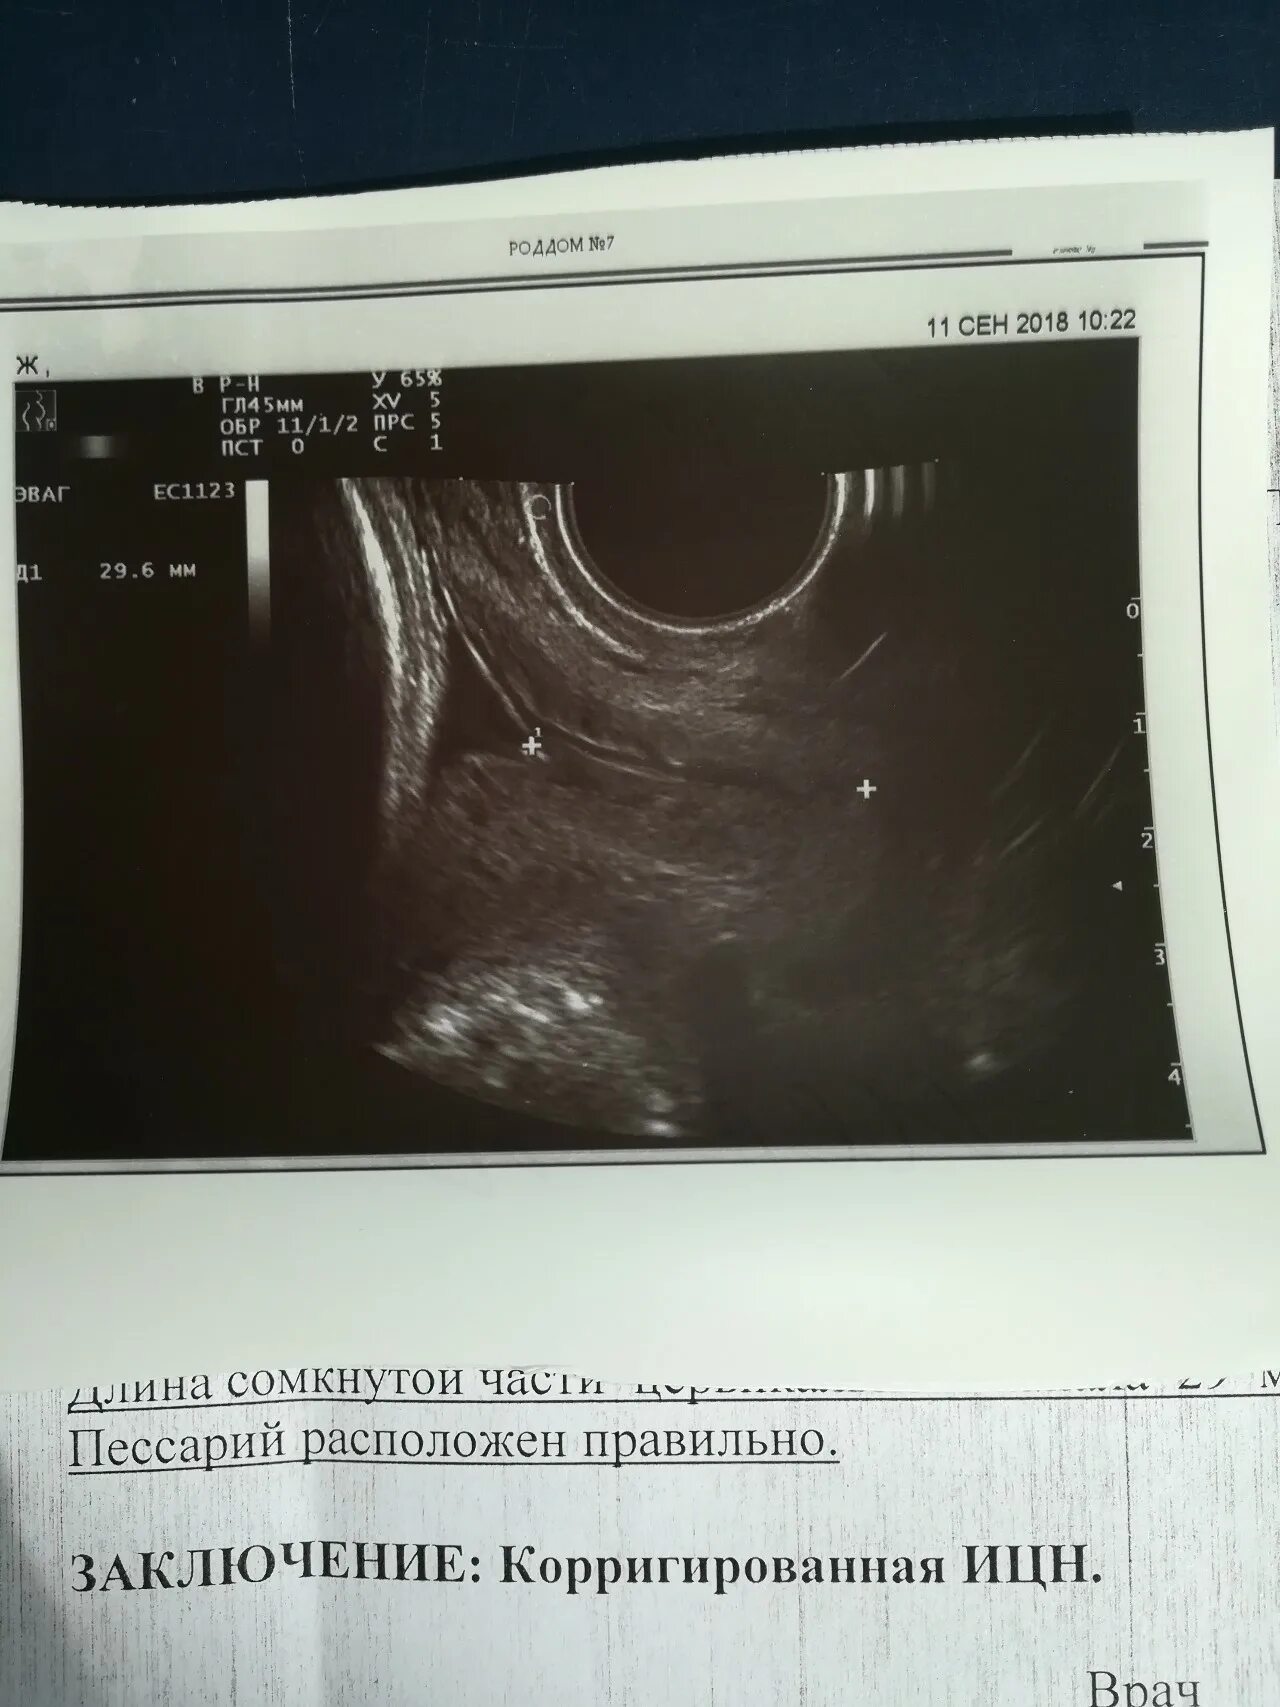

Цервикометрия как делают